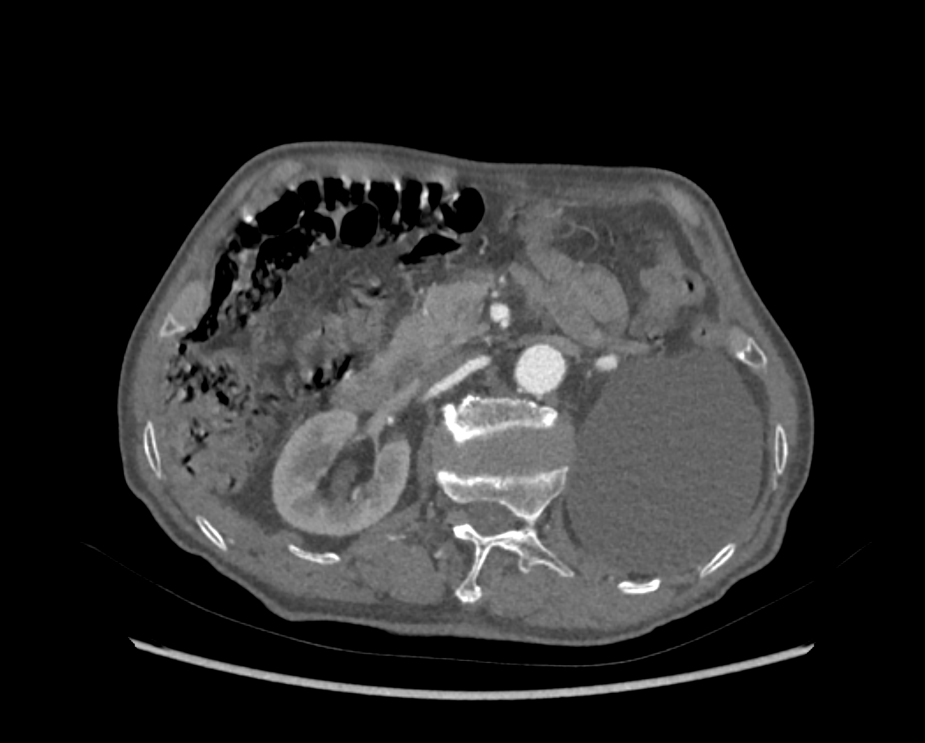

患者为74岁男性,2年前活动后出现胸闷、气短,休息后可以缓解。2021年5月症状加重,我院超声心动图提示:主动脉瓣反流(重度)、二尖瓣反流(重度),二尖瓣后叶脱垂(P2区)。左肾巨大囊肿,肾实质几不可见,左肾几无功能。

左肾巨大囊肿,压迫肾实质